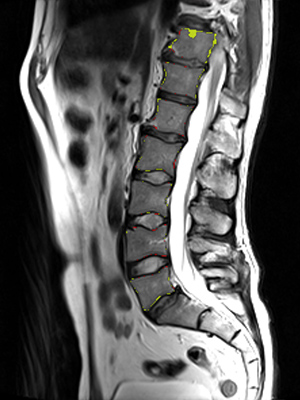

We trained and evaluated the method with five sets of CT and MR scans that visualize the spine. Reference segmentation masks for four of these datasets are publicly available, which allowed for a comparison with other publications that used the same data. Examples of images from the datasets are shown in Figure 3.

Similar performance was achieved for vertebra segmentation in various CT datasets with an average Dice score of and for vertebral body segmentation in an MR dataset with an average Dice score of . Surface distances were lower on CT images compared to MR images ( vs. ), however, there were also fewer training scans available in the MR dataset. Figure 4 illustrates the magnitude of differences of the automatic segmentations from the ground truth segmentations.

(a) Low-dose chest CT

(b) Lumbar spine CT (xVertSeg.v1 dataset)

(c) Lumbar spine MR